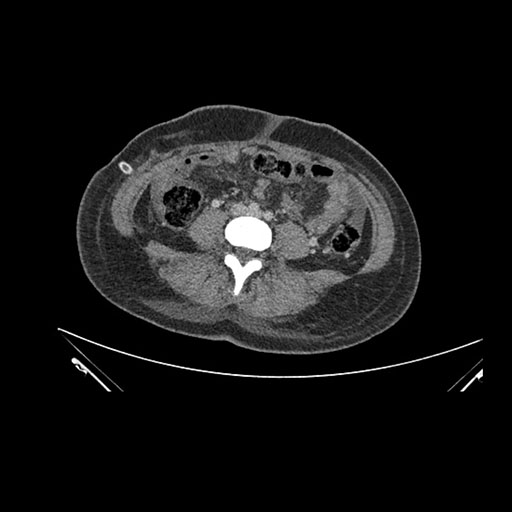

Axial Venous

Imaging analysis

Based on initial findings, which issue(s) would you be most concerned about?